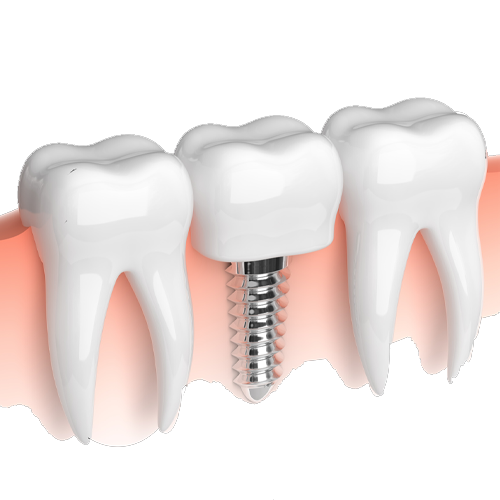

تاج دندان وریشه به خوبی با استخوان فک قرار خواهد گرفت .یک نوع پایه فلزی از جنس تیتانیوم که کاملا با بافتهای بدن سازگار است.این پایه قرار است در فک ورود و نقش ریشه رابازی نماید. برروی پایه ی فک بیرون پروتز ثابت که شبیه یک دندان اصلی است قرار خواهد گرفت.طی دهه های اخیر مواد و عناصر جدید زیادی در دندانپزشکی زیبایی کاربرد پیدا کرده اند.

از بدنه های اصلی که به صورت یک تکه و از جنس زیر کونیوم زیست سازگار طراحی شده اند .ایمپلنت دندانی زیر کونیوم دارای بیشترین حد کارایی و زیبایی طبیعی هستند و سلامت دهان را حفظ می کنند .شما به عنوان یک دندانپزشک در تجربیات خود دریافته اید حاضر در بازار نیاز تمام بیماران از بر طرف نمیکند.این امکان توسط سیستمهای جدید cad _ cam برای هربیمار اباتمنت های لازم توسط لابراتوار طراحی وبه بیماران ارائه گردد.